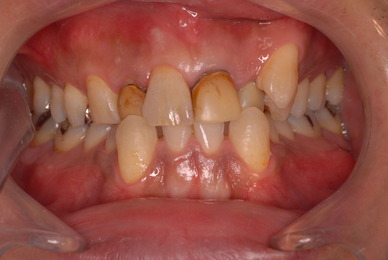

歯をいじられ体も心もボロボロになった患者さんからの手紙です。マスコミや権威などがいかにいい加減かわかります。歯は触らないほうがよろしいのです。

昭和60年代ぐらいから、私は歯を触るとか矯正するとかマウスピースをして顎の関節の症状を治癒するなどというような処置はしなくなってきました。

そもそも歯を触り何らかの金属やセラミックを入れる行為そのものが医学的には傷害処置ですから、なるべく避けるべき物なのです。